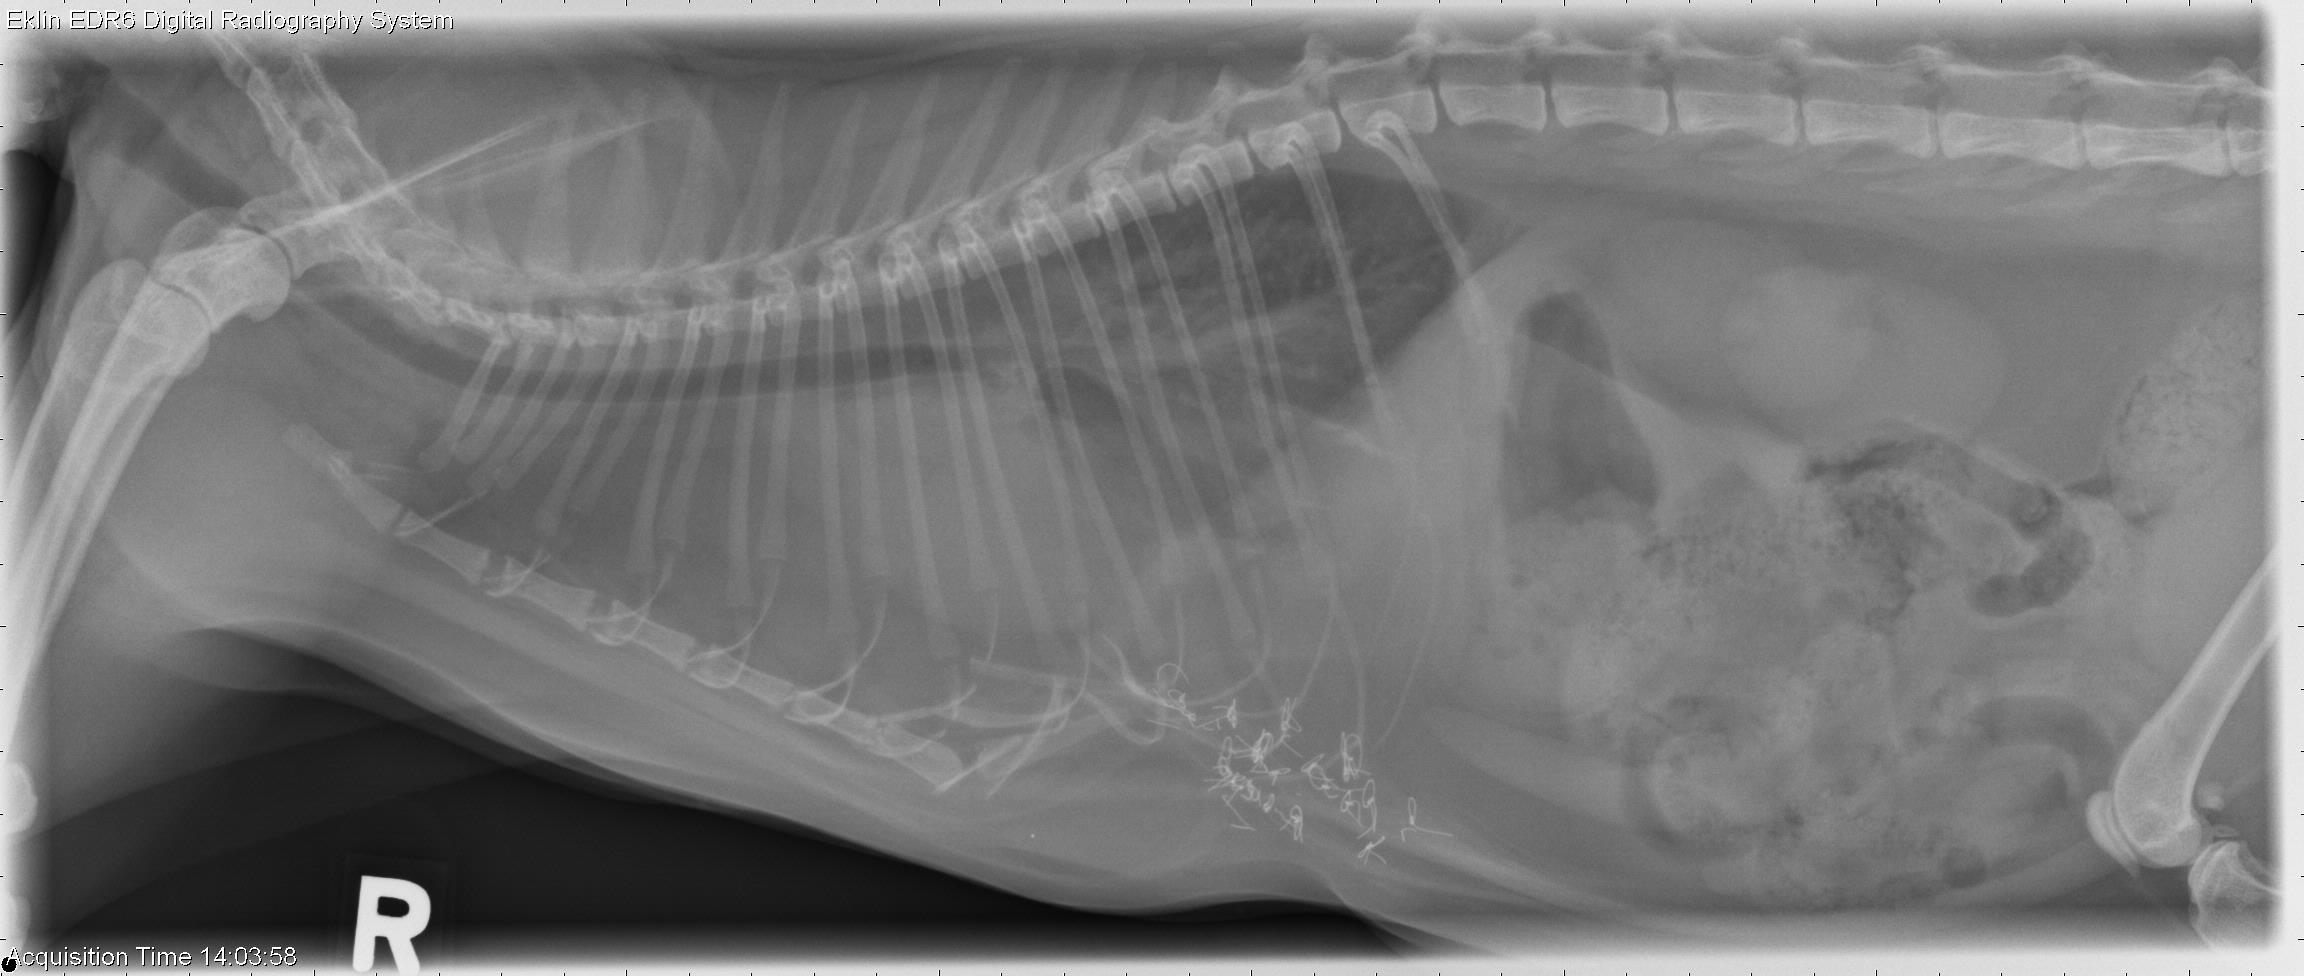

From www.veterinaryradiology.net

7 year old cat with dyspnea Dyspnea In Cats Video Learn about the causes and treatment of. is your cat breathing heavily? breathing problems (dyspnea) in cats can have a variety of causes, from a foreign body in the trachea to respiratory infections or allergies. • dyspnea in cats • discover the sounds of dyspnea in cats, from wheezing. cats can experience trouble breathing (known as dyspnea). Dyspnea In Cats Video.